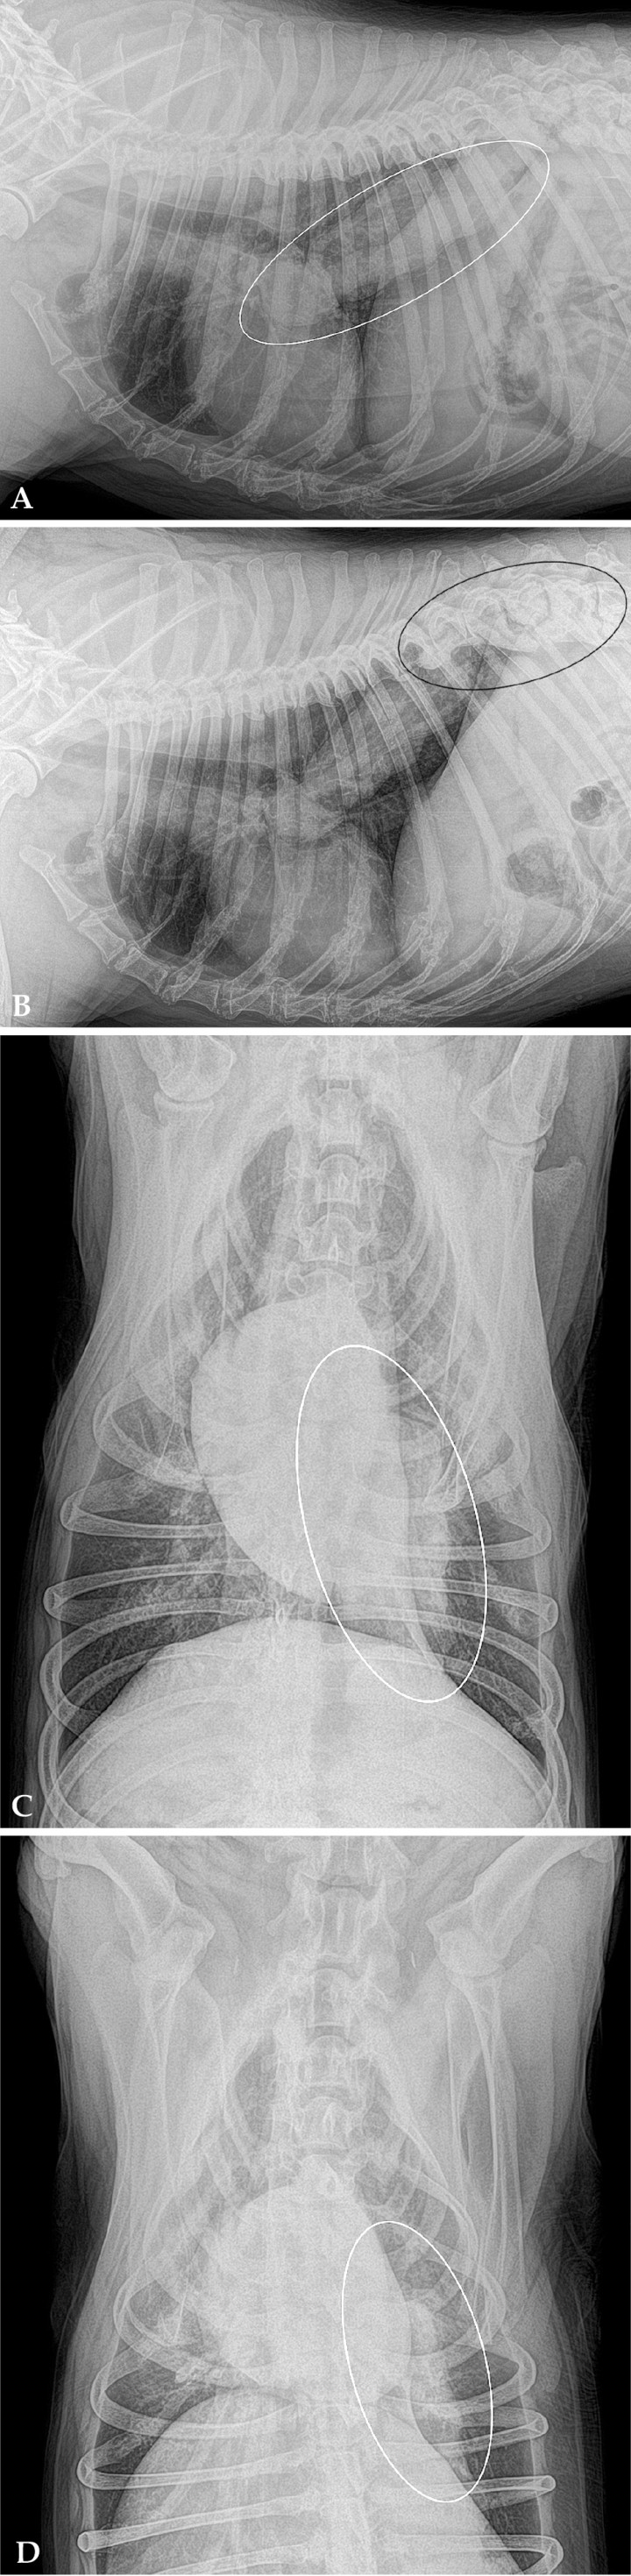

Se realizó un estudio radiográfico de la cavidad torácica, incluyendo cuatro proyecciones: lateral derecha, izquierda, ventrodorsal y dorsoventral (Fig. 1).

<p>Radiografías de tórax en un perro con decaimiento, inapetencia y fatiga de cuatro meses de evolución y episodios de tos no productiva en las últimas tres semanas. (A) Proyección lateral derecha. (B) Proyección lateral izquierda. (C) Proyección ventrodorsal. (D) Proyección dorsoventral.</p>

Radiografías de tórax en un perro con decaimiento, inapetencia y fatiga de cuatro meses de evolución y episodios de tos no productiva en las últimas tres semanas. (A) Proyección lateral derecha. (B) Proyección lateral izquierda. (C) Proyección ventrodorsal. (D) Proyección dorsoventral.

Se observa una masa de opacidad tejido blando, cilíndrica y de márgenes irregulares en el lóbulo caudal izquierdo, extendiéndose desde la carina hacia caudodorsal. El resto de estructuras intratorácicas no muestran alteraciones radiológicas significativas. A nivel extratorácico se evidencia una severa espondilosis, más acusada en T11, T12, T13, L1 (Fig. 2).

<p>Mismas imágenes que la Figura 1. Se observa una masa de opacidad tejido blando cilíndrica de márgenes irregulares en el lóbulo caudal izquierdo, extendiéndose desde la carina hacia caudodorsal (área delimitada en blanco). El área negra señala la espondilosis severa en T11, T12, T13, L1.</p>

Mismas imágenes que la Figura 1. Se observa una masa de opacidad tejido blando cilíndrica de márgenes irregulares en el lóbulo caudal izquierdo, extendiéndose desde la carina hacia caudodorsal (área delimitada en blanco). El área negra señala la espondilosis severa en T11, T12, T13, L1.